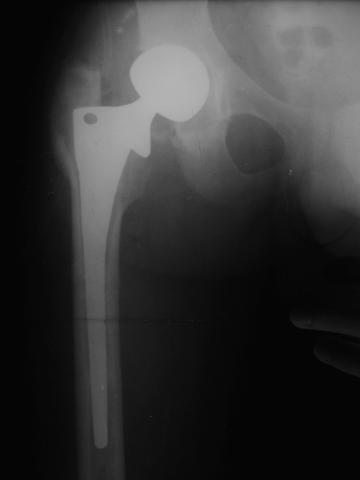

Лечился в стержневом аппарате по месту жительства. АВФ демонтировали через полгода из-за воспаления в области стержней (рис 2). После демонтажа в течение месяца больной лихорадил до 38*, были боли в бедре. Эти явления исчезли после курса антибиотиков. Через год после травмы в ЦРБ ему имплантировали биполярный протез (рис 3). Рана зажила первично. Ходил с костылями, слегка приступая на ногу. На контрольных осмотрах выявлена прогрессирующая протрузия (рис 4-6).